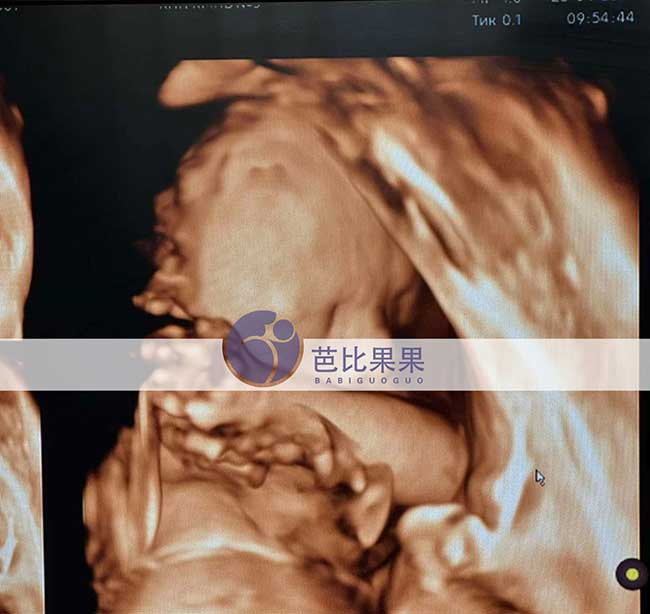

吴先生到乌克兰匹配的试管妈妈如期来做四维彩超啦!胎宝宝各项发育指标都稳稳达标,健健康康茁壮成长,每一次产检都是满心欢喜,静待可爱小天使平安到来。

吴先生到乌克兰匹配的试管妈妈如期来做四维彩超